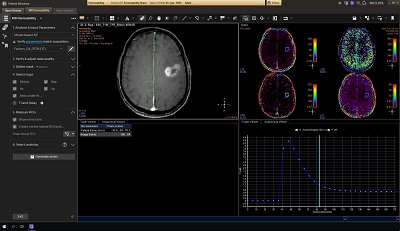

Permeability

Lesion characterization by reviewing vascular leakage

Designed to visualize T1 weighted DCE 3D datasets and assist in analyzing the tissue response.

• Calculates parametric maps such as Ktrans, Kep, ve and vf.

• The application has been validated for prostate and brain cancer.